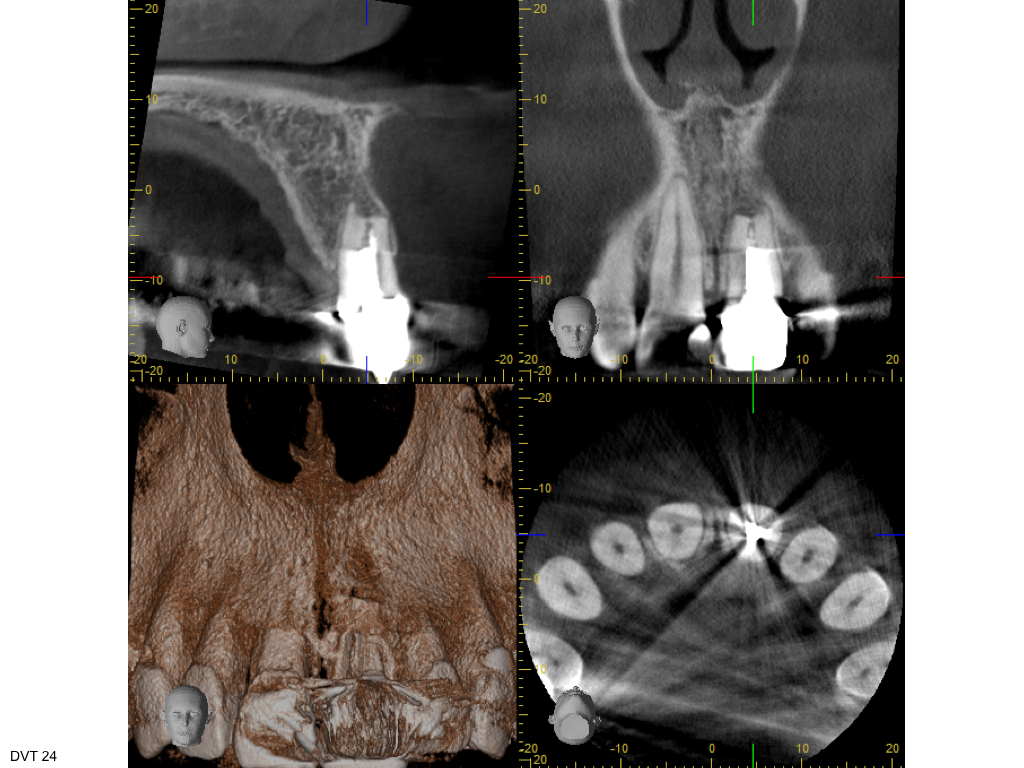

WS 04082016.002 Veröffentlicht 2. August 2016 am 1024 × 768 in Zustand nach traumatischer Zahnverletzung mit nachfolgender Wurzelbehandlung und Wurzelspitzenresektion